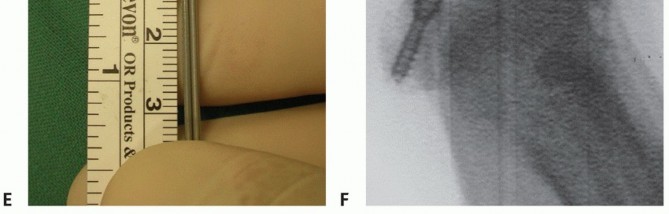

FIG 6 • Six-month follow-up weight-bearing radiographs after ORIF of medial sesamoid fracture/nonunion (patient in TECH FIGS 3, 4, 5, 6). A. AP view. B. Oblique view. C. Lateral view.

Clinical healing was documented with pedobarography (FIG 5A,B), and osseous healing of the fractures was proved by CT scan in three cases (FIG 5C). One screw had to be removed because of intermittent pain with exercise 1 year after surgery.

FIG 6 is 6-month follow-up radiographs of the patient in the case example.